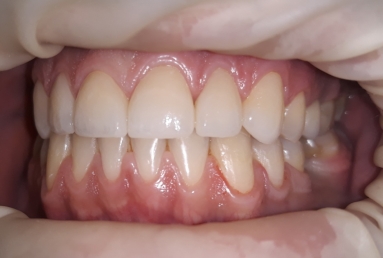

This patient has advanced dental abrasion due to bruxism ( clenching the teeth during the night). this is why the bite is modified and the frontal teeth are shorter. First stage of the treatment is wearing a night guard to relax the muscles and the temporo-mandibular jaw.

The final porcelain veneers for all frontal maxillary teeth are completed with tooth whitening and changing some composite fillings in lower frontals. On the lower left side a dental implant is inserted, on the upper right side external sinus lift is done. the treatment will be finalised with another upper implant, then two crowns on implants.